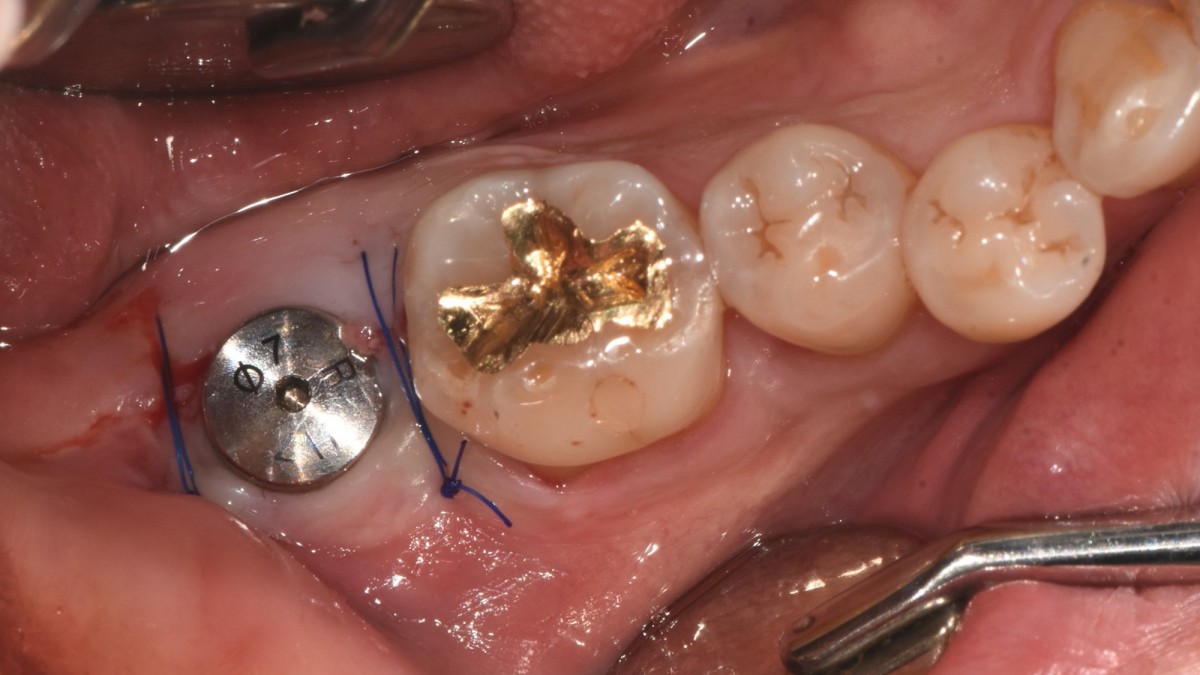

Single implant (staged) Arum NB1, f/u

A 47-year-old male patient had a crown with an ill-fitting margin and crack-tooth syndrome in the lower 2nd molar. No systemic issue.